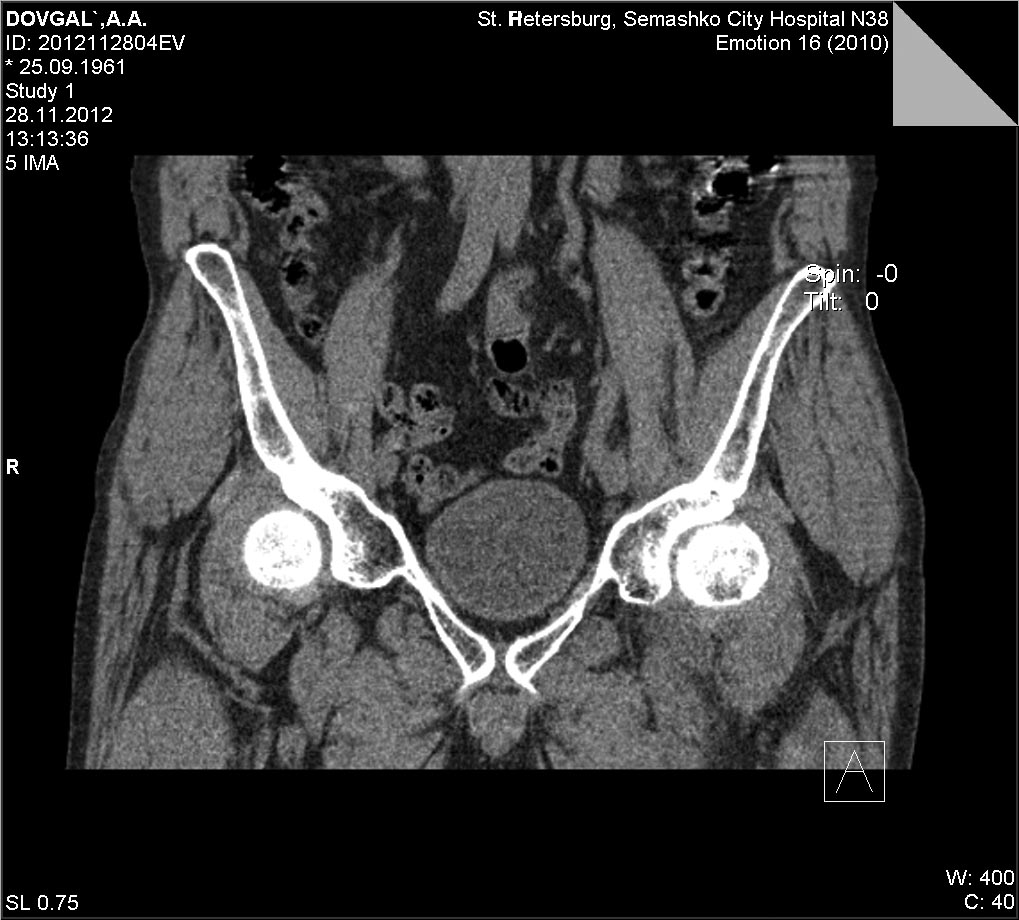

Доброго времени суток. Предлагаю к обсуждению случай с пациентом 51 года с переломом в передне-верхней зоне головки бедренной кости. С2.2 Мужчина, 51, направлен из травмпункта в наше ЛПУ с диагнозом " ушиб левого тазобедренного сустава". Со слов пострадавшего - 2 недели до поступления поскользнулся,упал с упором на левое колено. После чего появились боли в области левого тазобдренного сустава, боль при ходьбе, хромота, боль по передней поверхности тазобедренного сустава и в паху, боль усиливалась при осевой нагрузке, беспокоила в положении на спине, и на пострадавшем боку. Боль купировалась при сгибании в тазобедренном и коленном суставе в положении на спине. На стандартных рентгенограммах тазобедренного сустава патологии не выявлено.Госпитализирован в отделение с подозоением на импрессионный перелом головки бедренной кости Выполена компьютерная томография левого тазобедренного сустава, выявлено повреждение головки бедренной кости со вдавлением по передне-верхеней поверхности. На данный момент больному рекомендована разгрузка, ходьба без опоры на костылях до туалета, в остальном постельный режим. На обсуждение выносится ваш взгляд на дальнейшую тактику ведения больного, ваши наблюдения и предложения.В отделении мы рассматриваем следующие варианты: 1. Консервативное лечение с длительной разгрузкой, приемом хондропротекторов, сосудистых препаратов и т.д. 2. Возможность проведения ротационной остеотомии( есть небольшой опыт)

КТ

а был ли мальчик?сканы немного на разных уровнях, это просто место прикрепления связки, да и представить механизм такого перелома сложно, теоретически при заднем вывихе, но там обычно ломается по другому (Pipkin)

К сожалению это перелом, а не что иное, т.к. состояние сустава и отсутствие информации о другой патологии, кроме травмы(с учётом клиники) подтверждают диагноз. По классификации АО 31-С2.

Касаемо лечения - нового не придумано ни у нас, ни за бугром. Там более предпочетают оперативную репозицию. Но я уже писал, что хороший эффект возможен только в первые сутки. Далее результаты прогрессивно ухудшаются. Однако вопрос протезирования при данного типа повреждениях ставится не ранее, чем через 1 год. До этого периода идёт адаптация сустава и поскольку прогноз не известен, то и торопиться не надо. И ещё. Разгрузка сустава на скелетном вытяжении обязательна,т.к. уже виден формирующийся в этой зоне импиджмент-синдром, который может усугубить восстановление в суставе.